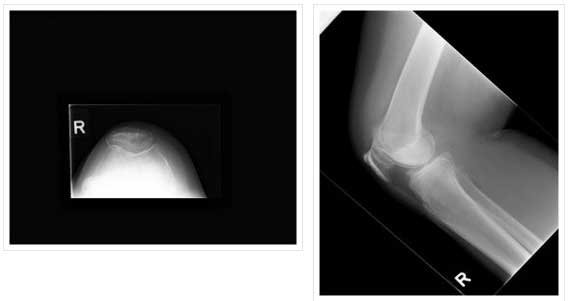

PATELLOFEMORAL

- PATELLA REPLACED WITH POLYTHYLENE INSERT

- TROCHLEA WITH UNCONSTRAINED METAL

- INLAY AND ONLAY TECHNIQUE: INLAY MY PREFERRED- LAZY

- PATELLAR TRACKING TO BE CLOSELY EXAMINED BEFORE SURGERY, MOST REQUIRE LATERAL RELEASE.